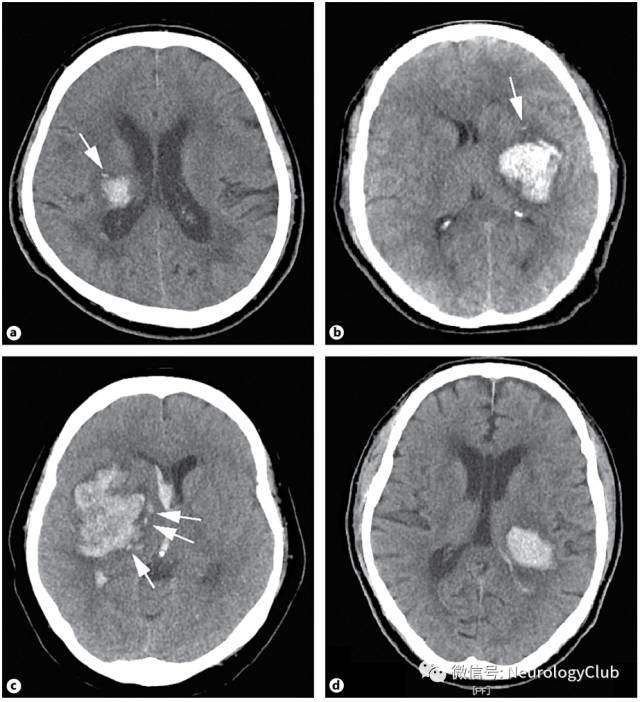

岛征

李琦等于2017年提出,其特征为CT平扫脑出血血肿周围的多灶性小出血。需满足以下两个标准中的任一条件即可定义:(1)存在≥3个分散小血肿全部与主要血肿分离或(2)存在≥4个小血肿,部分或全部与主要血肿相连。分散的小血肿好似分离的小岛,可以是圆形或椭圆形,与主要血肿分开。岛征预测ICH患者早期血肿扩大的敏感性、特异性、阳性预测值及阴性预测值分别为44.7%、98.2%、92.7%及77.7%。主要的血肿由破裂的血管出血引起,当该血肿在不断扩大时,可能导致邻近的小动脉损害,从而引起血肿周围出现海岛样不规则小血肿。岛征具有很高的特异性,可提示血肿扩大,其出现也意味着脑出血患者预后不良。在一些文献上也称主要血肿周围的小出血灶为“卫星征(satellite sign)”,其定义:CT平扫≥1个平面上邻近但与主要血肿分离的小出血(最大直径<10mm),卫星灶和主要血肿的最短距离为1-20mm。有学者研究认为其对预测血肿扩大及预后不良也有价值。

(图7:脑出血岛征)

(图8:a-c:脑出血卫星征;d:脑出血未见卫星征;注意其与岛征定义上的不同)